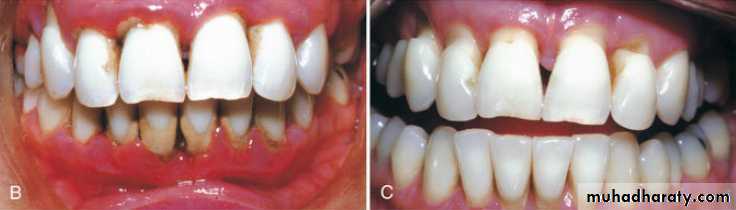

Transfer of the patient from active treatment status to a maintenance program is a definitive step in total patient care that requires time and effort on the part of the dentist and staff.Patients who are not maintained in a supervised recall program subsequent to active treatment show obvious signs of recurrent periodontitis (e.g., increased pocket depth, bone loss, or tooth loss).

The recall examination is similar to the initial evaluation of the patient. However, because the patient is not new to the office, the dentist or hygienist primarily looks for changes that have occurred since the last evaluation.Updating of changes in the medical history and evaluation of restorations, caries, prostheses, occlusion, tooth mobility, gingival status, and periodontal and peri implant probing depths are important parts of the recall appointment.

Recurrence of Periodontal DiseaseOccasionally, lesions may recur, which is often due to inadequate plaque/biofilm control on the part of the patient or failure to comply with recommended SPT schedules.